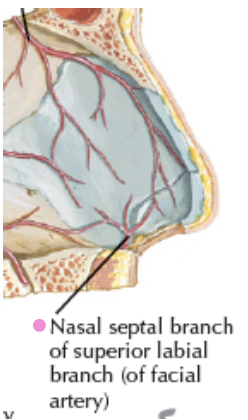

Artery

- Dorsal nasal a.

- External nasal a.

- Nasal br.

- Septal a.

- Alar a.

Artery

-

- 供應鼻中隔

-

- Septal br.

- Septal br.

-

- Sphenopalatine a.

- to Incisive canal

- Greater palatine a.

- Sphenopalatine a.